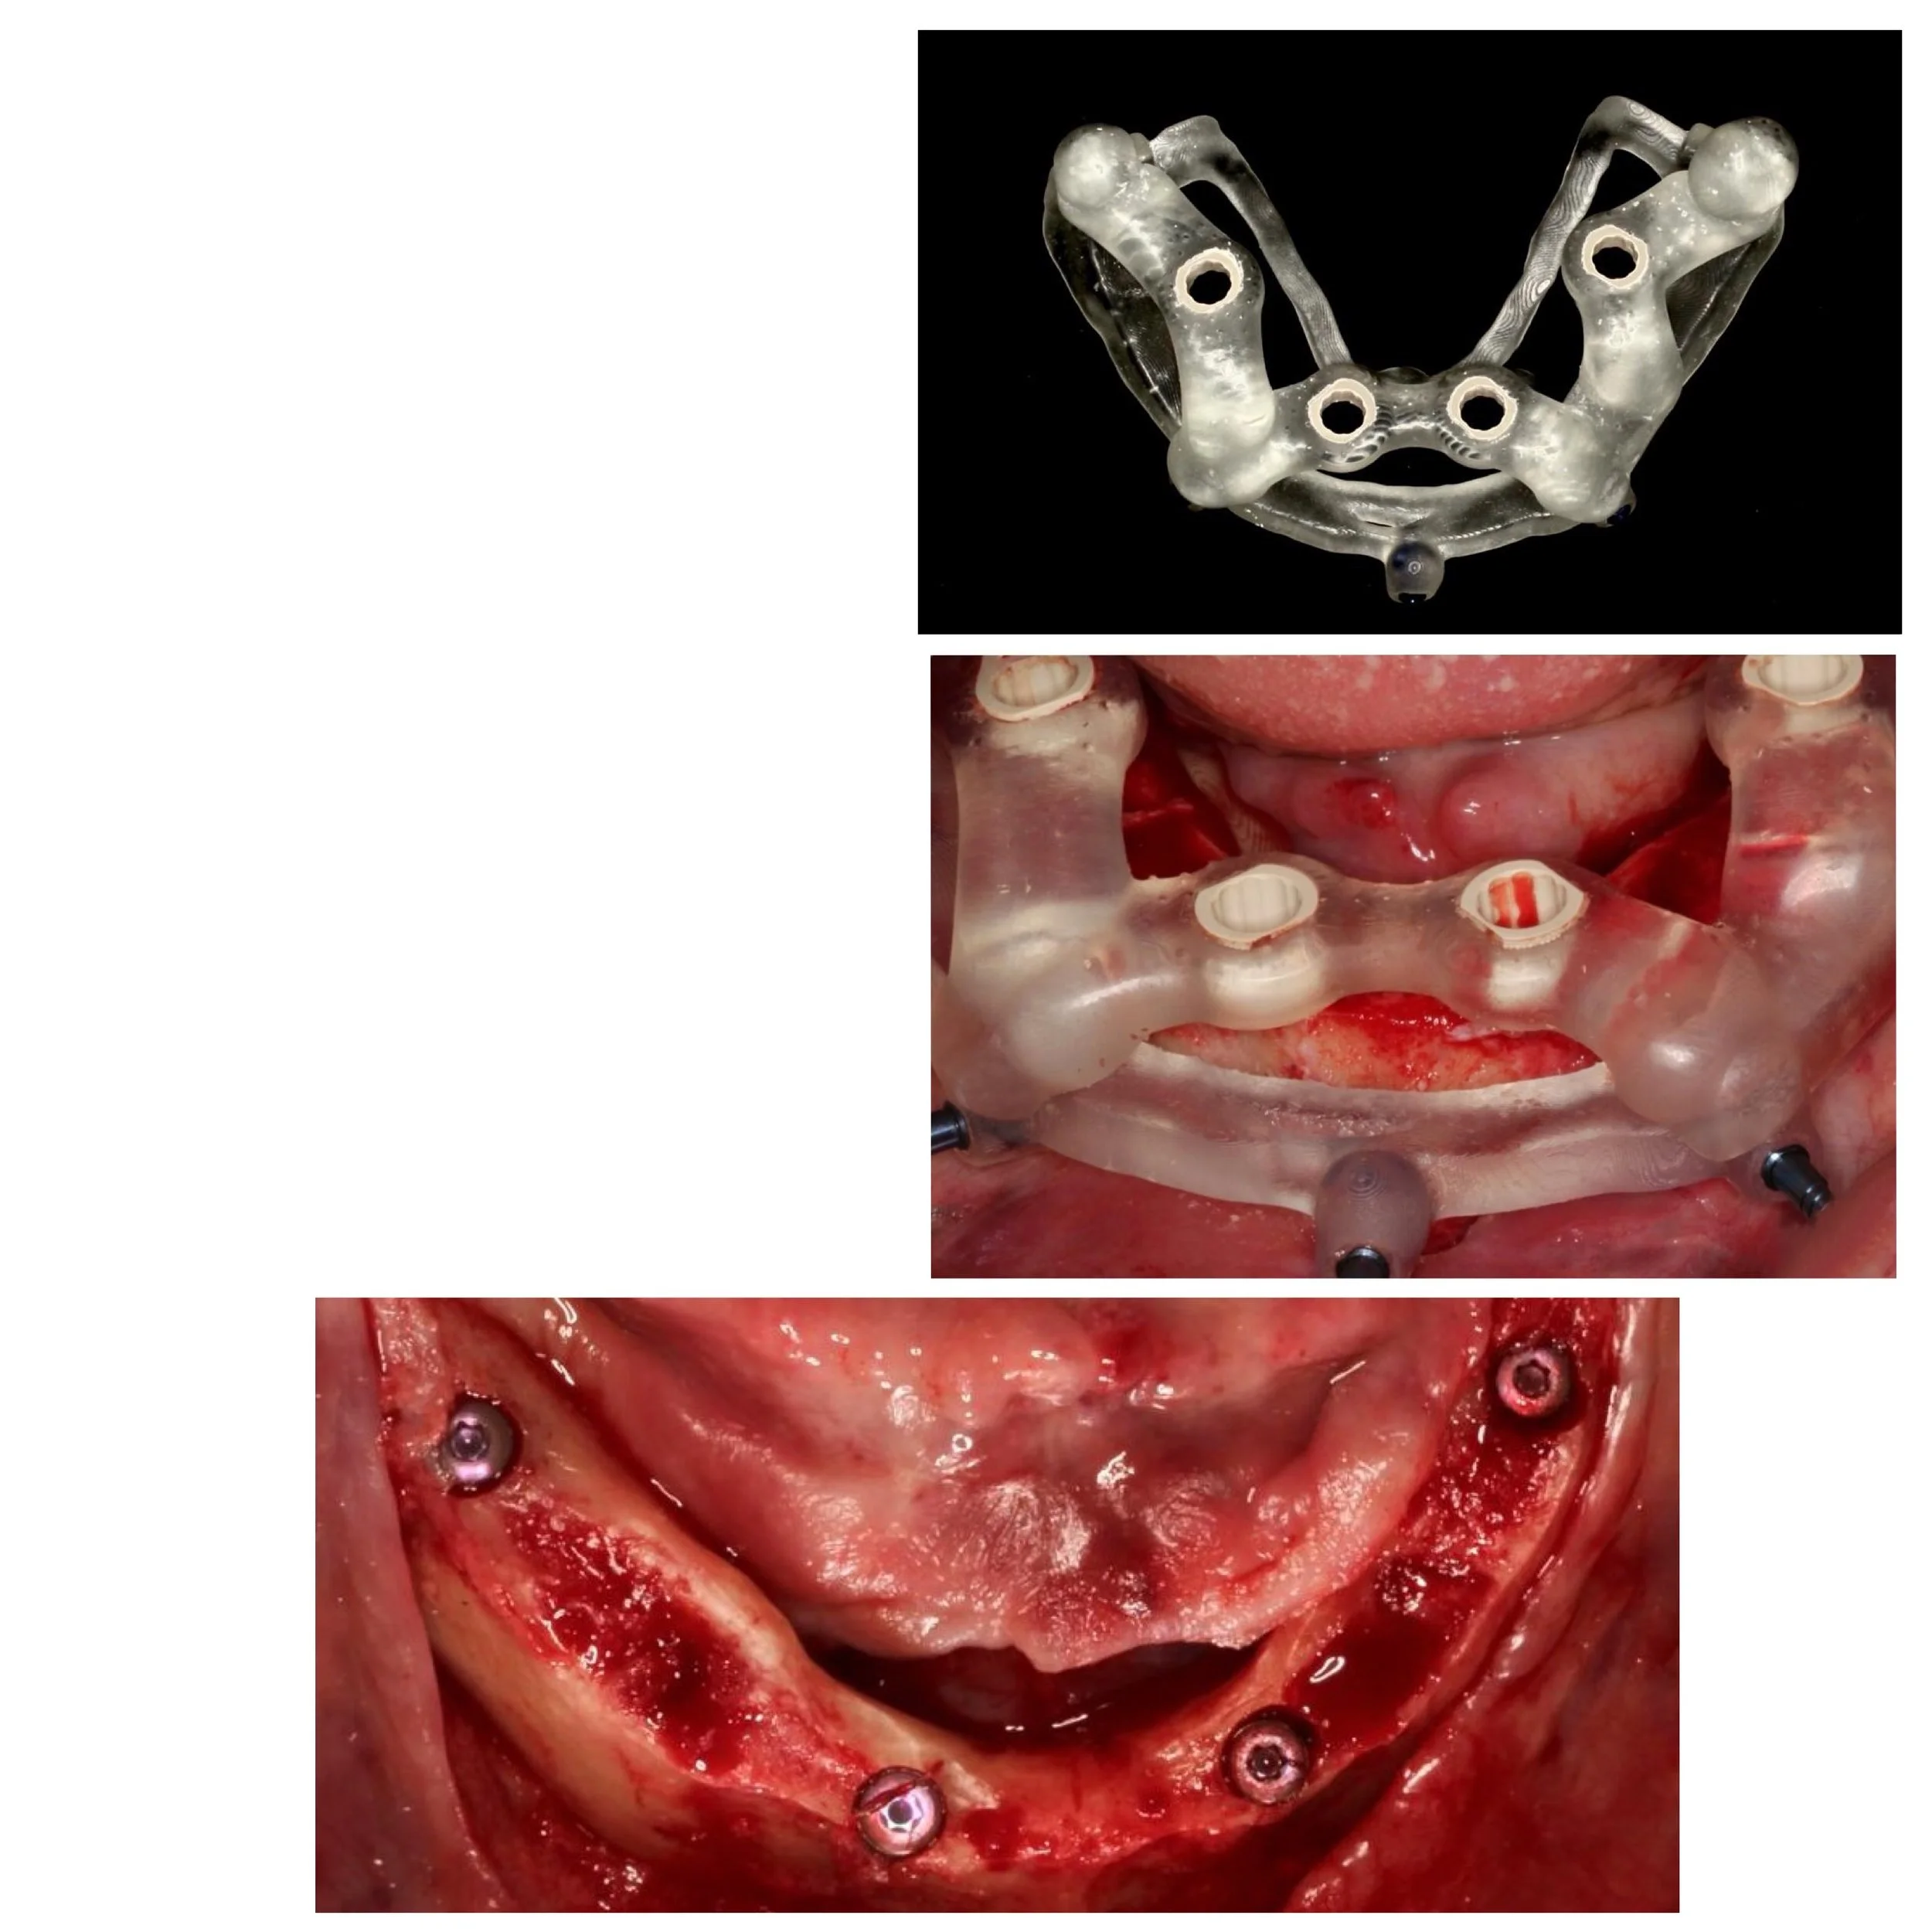

For patients who are missing most or all of their teeth in an arch, the All-on-X protocol (often All-on-4 or All-on-6) is a life-changing solution. Instead of one implant per tooth, we strategically place a specific number of implants (the "X") to support a full bridge of teeth.

1. 3D Imaging & Planning: We use CT scans to evaluate bone density and plan the exact placement of each implant.

2. Surgical Precision: Our periodontist performs the surgery in the comfort of your home office.